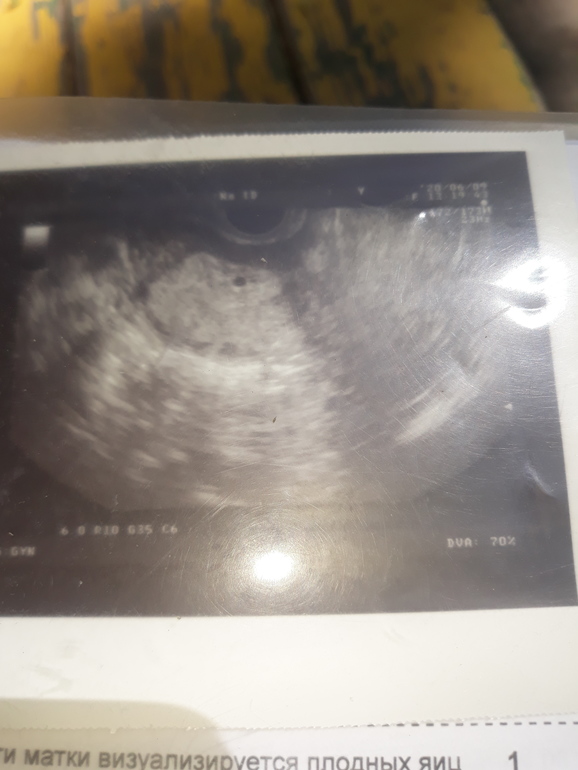

Знаете, я тоже этого не понимала, когда мол смотрите я вижу,вижу.. а ты смотришь и думаешь ну белый как лист бумаги.. но это сайт для беременных,и тех кто планирует б. Как мой муж говорит## планета ## а значит и люди здесь такие.. кто ждет заветные 2 полоски годами.. я вот для разнообразия предлагаю как многие тут выражаются (поломать глазки) но не в поисках полосок, а по фантазировать.. кто что видит на этом снимке?

Я в узи ничего не понимаю 🤷‍♀️. Вижу белые потертости на чёрном фоне 😂😂😂

Ну если по фантозировать можно увидеть всё что угодно.. например зародыша, или рыбу,змею... или 👍класс!! Если увеличить.. это все фантазия,,обман зрения.